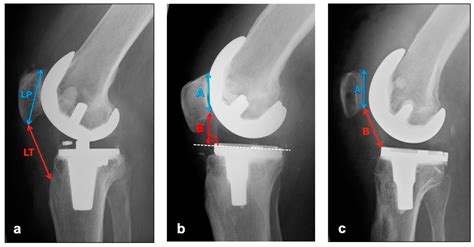

Diagnosing patella tracking problems typically involves a combination of a physical examination and imaging tests. A healthcare provider will assess the knee's range of motion, strength, and alignment, and may perform specific tests to evaluate patellar tracking. Imaging studies, such as X-rays, MRI, or CT scans, can provide detailed views of the knee joint and help identify any underlying structural issues.

• Tibial Tubercle Osteotomy: This procedure involves realigning the tibial tubercle, the bony prominence on the tibia where the patellar tendon attaches, to improve patellar tracking.

• Patellar Realignment: In severe cases, a more extensive surgical procedure may be required to realign the patella and correct any underlying structural issues.